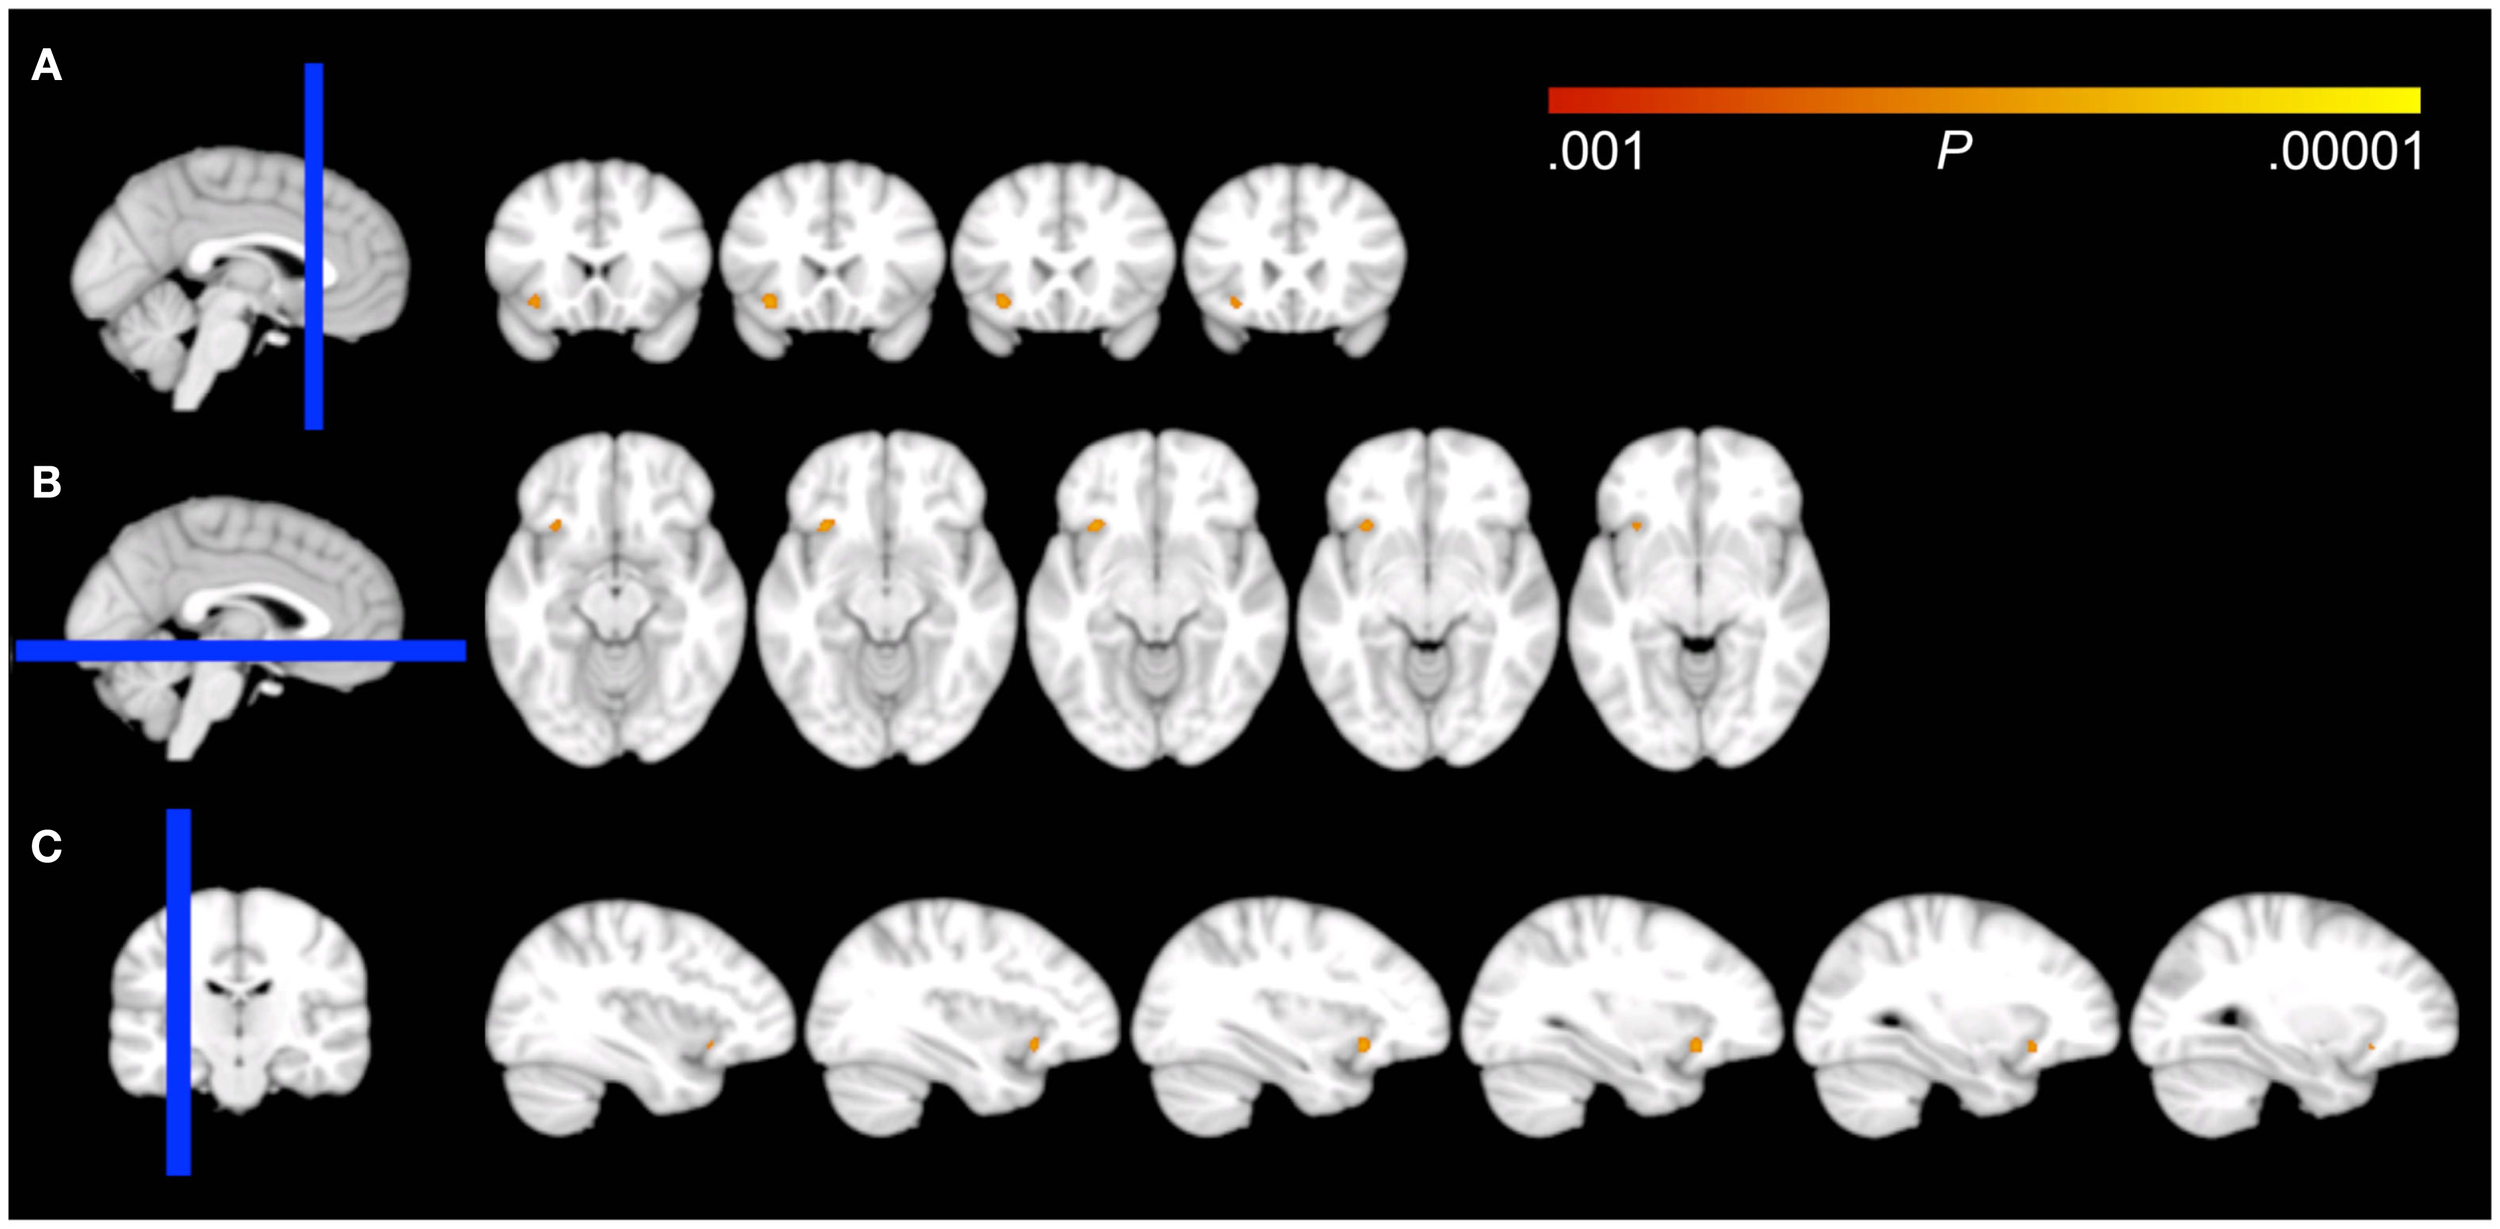

Voxel-wise analysis showed that the EMA compound Z-score significantly predicted GM density in a 66 voxel, 0.223 cc cluster at P < 0.001 uncorrected. The complete cluster was located within our 16 mm radius spherical ROI and the peak voxel (approximate MNI coordinates = −30, 13, −13) survived correction for multiple comparisons (P = 0.029, family wise error voxel-corrected). An auxiliary analysis, using mid-sleep time on free days (corrected for sleep debt) instead of EMA to predict GM density, showed no significant voxels within our ROI at P < 0.001 uncorrected. The cluster for EMA encompassed the region where the left inferior OFC borders with the most anterior aspect of the insular cortex (Figure 1). The association of EMA with the average GM density within this cluster (i.e., an average of the GM probabilities for each voxel in the cluster) is visualized in the scatterplot of Figure 2; EMA explained an additional 6% of variance on top of the other predictors age, sex, total GM volume, and imaging site. Voxel-wise analysis at P < 0.001 uncorrected within our ROI showed no significant association of GM density with either DIS or DMS.

Figure 1

Effects of voxel-based regressions. A cluster of voxels is shown in which GM probability was a significant predictor for the early morning awakening compound Z-score, overlaid on all coronal (A), axial (B), and sagittal (C) 1.5 mm slices that contain the cluster from the DARTEL template, according to neurological convention (left = left). The blue bar in the localizer on the left side of the panels represents the slab of which slices are shown on the right. Note that the cluster overlaps the border of the inferior part of the orbitofrontal cortex and the most anterior aspect of the insular cortex.